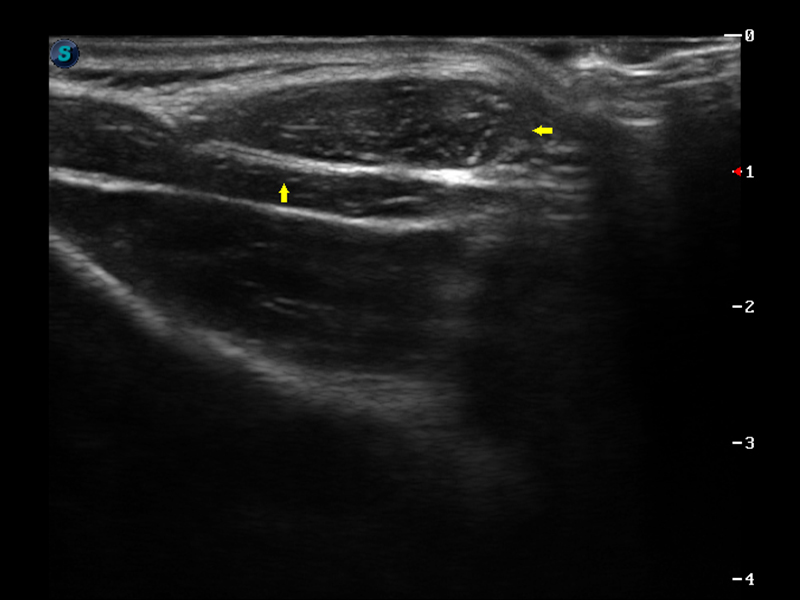

S9便携式彩色多普勒超声诊断仪是诸侯快讯官网研发的高端便携彩超设备,外观设计新颖、产品性能卓越。S9在便携超声领域采用了突破传统的触摸屏交互设计,并以先进的软件硬件技术和设计理念,为您带来清晰的图像质量、稳定的工作性能和便捷的操作体验。